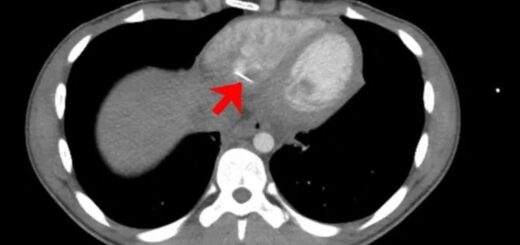

Θάνος Ξυδόπουλος Μελέτη διαπίστωσε ότι όσο μεγαλύτερη είναι η δραστηριότητα στα νευρικά κύτταρα στην περιοχή της αμυγδαλής του εγκεφάλου, τόσο πιο γρήγορα μπορεί να αναπτυχθεί η κατάσταση γνωστή ως σύνδρομο Takotsubo (TTS). Το Τακοτσούμπο, επίσης γνωστό ως σύνδρομο...